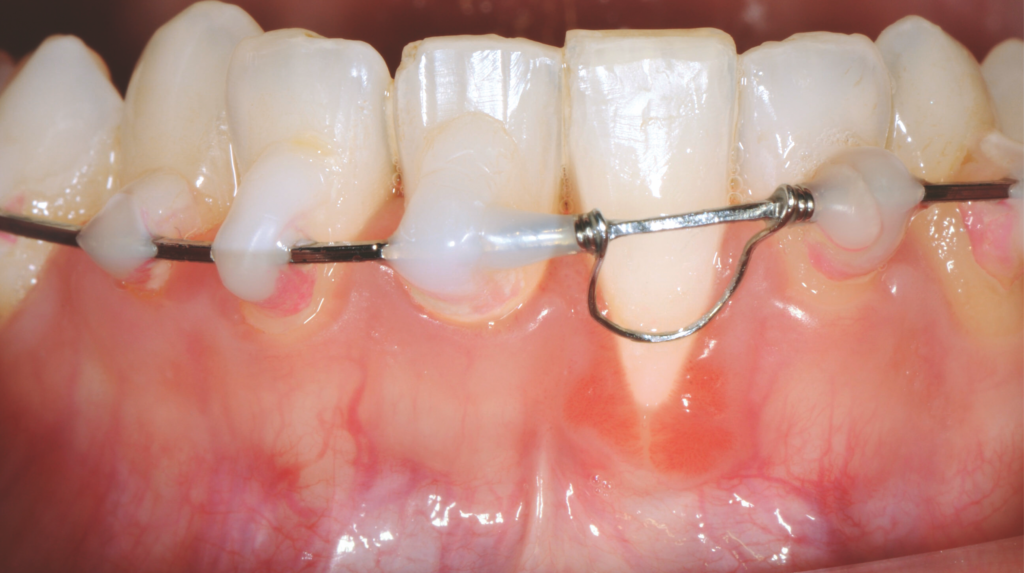

Perhaps the greatest challenge lies in the capture of soft tissue emergence profiles when the tissue phenotype is thin and less stable or when an implant is deeply positioned in tissue and bone and difficult to scan the prosthetic tissue envelope. It is important to remember that it is absolutely acceptable to introduce analog steps like standard impressioning if necessary. Tissue scanning challenges can be managed by scanning or impressing the provisional restoration outside of the mouth to record the emergence profile if it is satisfactory.

IOS, intraoral scanning.